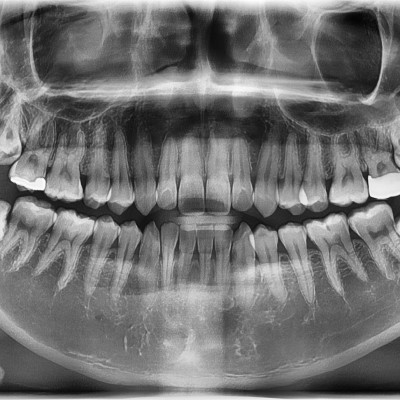

#48 사랑니 발치 (#47 포함) #48 사랑니 발치 (#47 포함) 구강 외과 전문의가 당일 발치했습니다. --------------------..

작성자 이턱이 작성일 03-11 조회 22